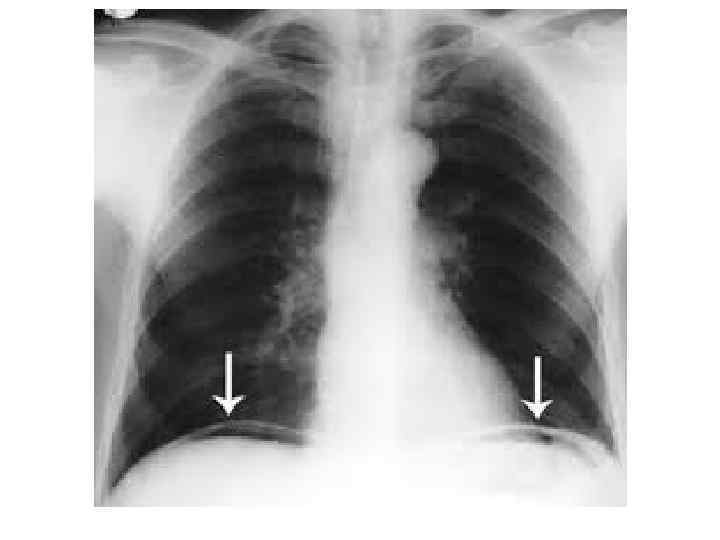

Повреждение полых органов быстро осложняется перитонитом, который про является сухостью языка, тахикардией, пострадавший щадит брюшную стенку при дыхании, пальпация выявляет напряжение брюшной стенки и выраженную болезненность, симптом Щеткина—Блюмберга положителен. При разрыве полого органа в брюшную полость поступает свободный воздух, который скапливается под диафрагмой, что при перкуссии создает впечатление сглаженной печеночной тупости.